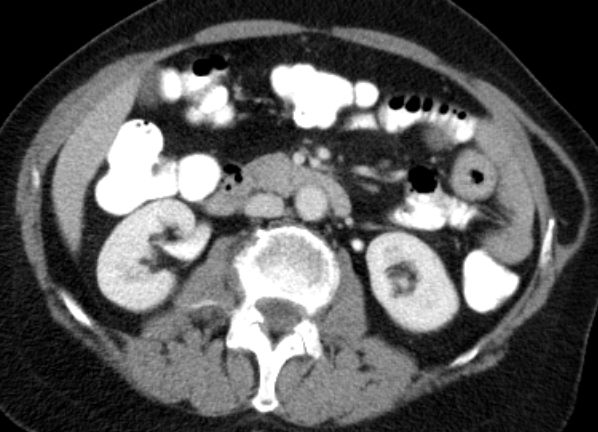

Colon 79-jährige Frau mit einem Tumor im Zoekum. Bei der Operation fand sich im Bereich der Ileozökalklappe ein unregelmäßig gestalteter, teils ulzerierter und teils polypös erhabener, 42 mm großer, derber Gewebsbezirk. Histologie: In soliden Komplexen und Strängen angeordnete, relativ große Tumorzellen mit deutlicher Zell- und Kernpolymorphie. Vergrößerte Zellkerne mit aufgelockerter Chromatinstruktur und ab und an prominenten Nukleolen. Schmaler oder kaum erkennbarer Zytoplasmasaum. Vermehrt typische und atypische Mitosen. Tumoreinbruch in Blut- und Lymphgefäße. Das CT zeigt multiple Lebermetastasen.